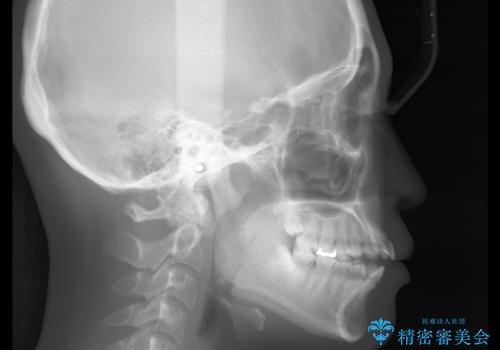

前歯で噛めない:オープンバイト(開咬)を非抜歯インビザラインで治療

- 上下の歯が噛んでいないことを気にしてご相談にいらした方です。

オープンバイトの方への治療は、通常抜歯を行いワイヤーによる矯正治療を行うことが多いですが、今回はインビザラインの特性を生かし、非抜歯にて綺麗な歯並びを作ることが出来ました。